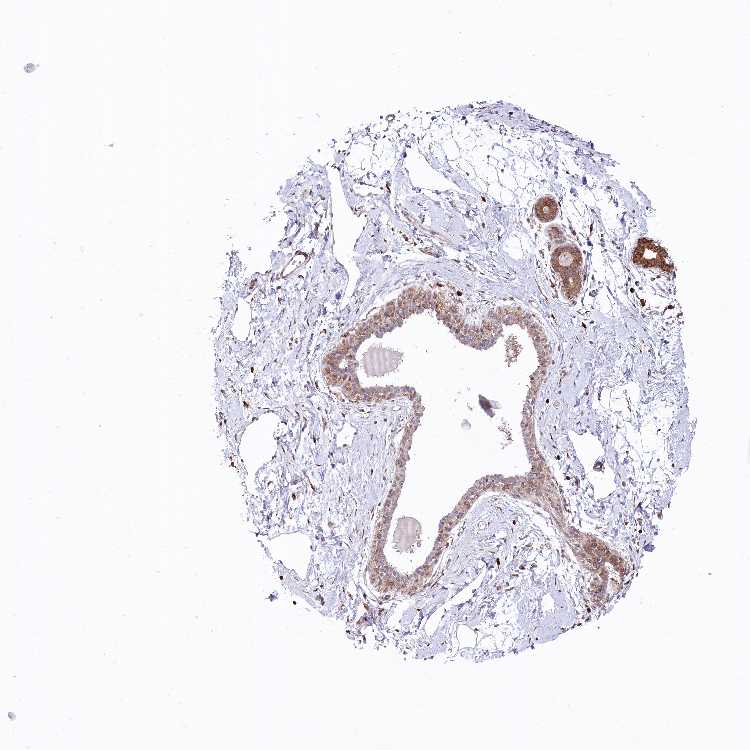

BREAST - Antibody stainingi

Antibody staining in the annotated cell types in the current human tissue is reported as not detected, low, medium, or high, based on conventional immunohistochemistry profiling in selected tissues. This score is based on the combination of the staining intensity and fraction of stained cells.

Each image is clickable and will lead to virtual microscopy that enables deeper exploration of all samples and also displays staining intensity scores, fraction scores and subcellular localization as well as patient and tissue information for each sample.

Antibody HPA039374

Adipocytes Not detected

Glandular cells Medium

Myoepithelial cells Medium